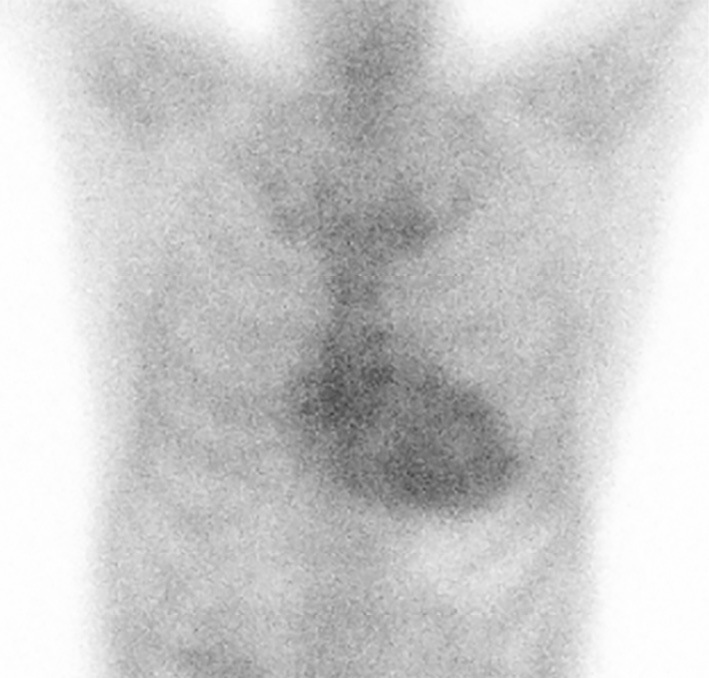

心脏淀粉样变性(CA)主要由淀粉样转甲状腺素(ATTR)或免疫球蛋白轻链(AL)引起,预后差,准确的诊断至关重要,因为两种疾病的最佳治疗方法不同。然而,诊断AL- ca具有挑战性,因为无法获得有效的AL检测抗体,特别是在AL-和atr - ca共存的情况下。本报告报告了一例成功诊断的复杂AL-和atr - ca,并成功地使用他法非地治疗atr - ca和联合化疗治疗AL- ca。该病例强调了CA精确诊断的重要性,并支持了并发淀粉样变性同时治疗的有效性和安全性。

Cardiac amyloidosis (CA), predominantly caused by amyloid transthyretin (ATTR) or immunoglobulin light chain (AL), has a poor prognosis, and a precise diagnosis is crucial because the optimal treatments differ between the two conditions. However, diagnosing AL-CA is challenging because of the unavailability of effective AL-detecting antibodies, particularly in cases with coexisting AL- and ATTR-CA. This report presents a successfully diagnosed case of complicated AL- and ATTR-CA that was successfully treated with tafamidis for ATTR-CA and combination chemotherapy for AL-CA. This case highlights the importance of a precise diagnosis of CA and supports the efficacy and safety of concurrent treatment for coexisting amyloidosis.